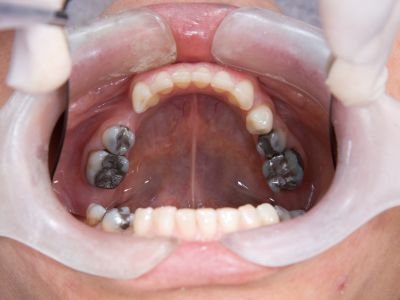

🫵🏼Reservamos la agenda con los especialista que requieras

Hacemos un tour virtual por nuestra instalaciones para que sientas la seguridad confianza de visitarnos, cuidamos cada detalle.